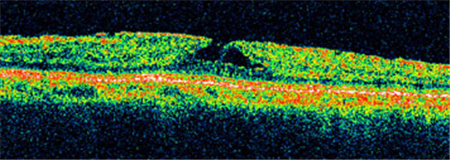

Ⅰ期黃斑裂孔通常無需手術(shù),若裂孔惡化至Ⅱ-Ⅳ期就需要考慮進(jìn)行手術(shù)治療。上海眼科醫(yī)院排名通過學(xué)相干斷層掃描來診斷黃斑裂孔,可清楚照出玻璃體及視網(wǎng)膜的情況,了解患者黃斑裂孔的大小、位置等。